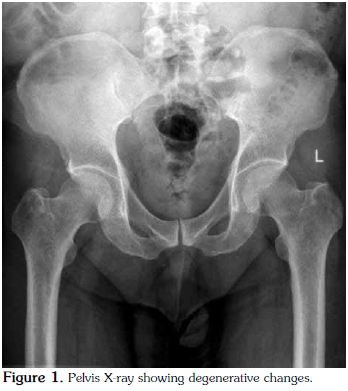

The patient was then admitted for further investigation. From an analytical point of view, there was an increase in acute phase reactants [C-reactive protein (CRP) 95.2 mg/L and erythrocyte sedimentation rate (ESR) 87 mm/hr]. Microcytic anemia was also present (hemoglobin 11.2 g/dL, mean erythrocyte volume 79.4 fl, and iron 37 mg/dl), but the ferritin and serum levels were normal as were the total iron binding capacity and transferrin saturation rate. Serum protein electrophoresis revealed a decrease in albumin (47.3%), whereas the alpha 1 (16.1%), alpha 2 (14.9%), and gamma globulin (21.3%) levels were higher. Other immunological tests determined that the rheumatoid factor (RF), anticyclic citrullinated peptide (anti-CCP), antinuclear antibody (ANA), complement, and anti-doublestranded deoxyribonucleic acid (anti-dsDNA) levels were normal, and the serum uric acid levels were also within normal limits. Furthermore, the primary and secondary tuberculosis screening tests were negative, and the serology tests for Brucella, Chlamydia, the human immunodeficiency virus (HIV), and hepatitis B and C were negative as well. Human leukocyte antigen typing revealed the presence of A1, A2, B41, B57, Cw6/7, DR11, and DR13 while a urinary system ultrasound and an intravenous pyelogram were normal. An X-ray of the pelvis showed degenerative changes (Figure 1), and because of the patient's ongoing lower back pain and peripheral joint swelling, magnetic resonance imaging (MRI) of the sacroiliac joints was performed, which showed periarticular edema of the sacrum in the anterior segment along with a slight increase in sclerosis of the right sacroiliac joint in the anterior superior segment. Slight edema of the left periarticular sacral area was also seen in the posterior segment. We then recommended that the MRI findings be interpreted in accordance with the clinical picture.